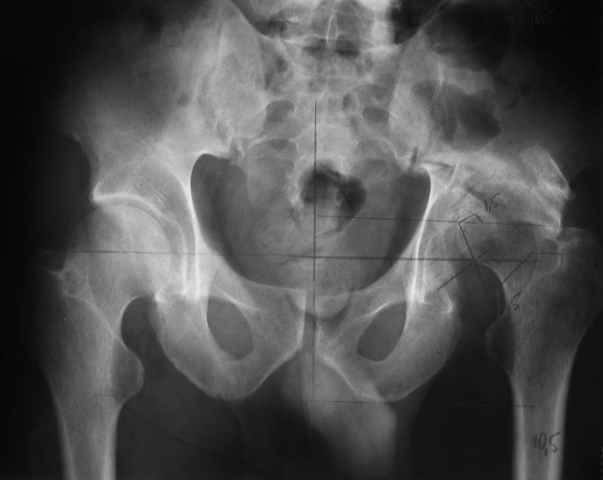

Dear All, The patient came to us for opinion regarding this # of pelvis which he sustained 5 months back.

He gives history of being on skin traction for 3,5months. After that he was advised partial weight bearing to be graduated to full weight bearing. Now the patient has difficulty in weight bearing as it is painful. He can walk a few steps only with the help of a walker. Hip movements are restricted and painful. Fl-90* ER-10* IR-0, shortening-4cm. He also had # of humerus and radius/ulna, which were plated and have united. The serial x-rays of the pelvis/Hip during these 5 months show that the hip joint has been in the same position. I have the CT pictures also but not digitalized as yet.

He is 47 years old, Class-1 officer.What are the options? Expert comments please.1. # Pelvis stabilization - Is it possible at 6 mths? And subsequently THR.

2. THR in this position- Cup positioning in a deformed pelvis?

It is a displaced and ununited fracture of the acetabulum, probably type C (AO). The pelvis is not fractured from what one can see of the sacro iliac joint.

Sorry missed the wide open pubic diastasis.